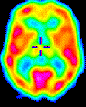

• To use neuroimaging technologies to understand how cognitive behaviors are coded in the human brain.

transverse_pet2